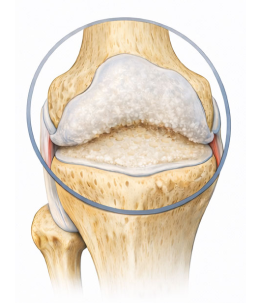

Degenerative arthritis퇴행성관절염은 연골이 반복적인 자극과 노화로 인해 손상되면서 염증과 통증을 유발하고,

결국 움직임에 제한을 가져오는 질환입니다.

다양한 요인으로 연골에 지속적인 자극이 가해지면서 관절을 보호하는 능력이 크게 감소하게 됩니다.

정상적인 모습

환자의 모습